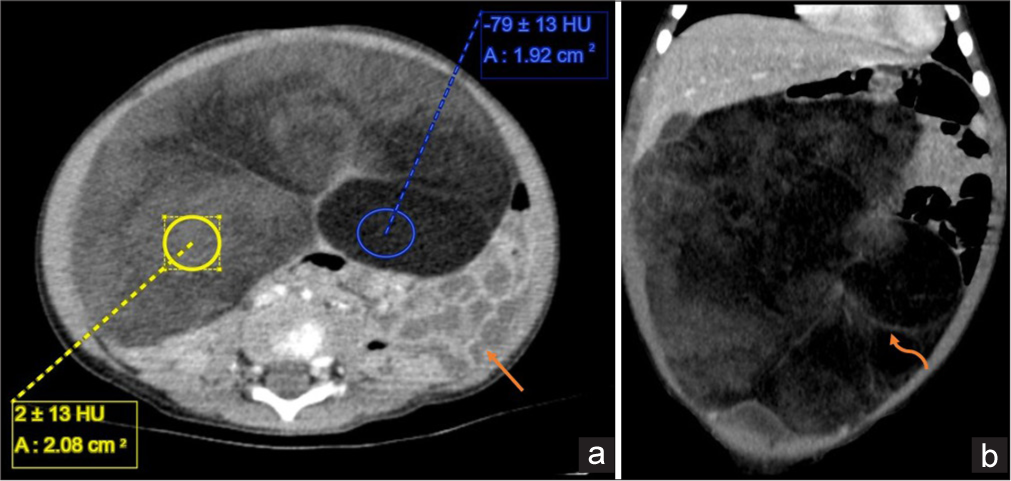

A subsequent contrast-enhanced computed tomography (CT) scan of the abdomen demonstrated a large, lobulated mass with predominantly fat attenuation, interspersed with thin, enhancing septae and small isoattenuating solid areas [Figure 2]. The mass extended superiorly to the transverse colon and the left lobe of the liver, while inferiorly, it reached into the pelvis, abutting the dome of the urinary bladder. Anteriorly, it contacted the peritoneal cavity. The lesion itself was positioned anterior to the small bowel loops, which were displaced posteriorly.

There was no evidence of extension into the retroperitoneal space or the lesser omentum. No infiltration into surrounding structures was observed. In addition, the lesion lacked calcifications, and significant lymphadenopathy was absent. Based on its location and the observed pattern of mass effect, the imaging findings strongly suggested that the tumor had originated from the greater omentum.

- A 1-year-old boy with omental lipoblastoma, Contrast enhanced CT abdomen (a) axial and (b) coronal sections shows a large, lobulated mass that fills the entire abd omen. It is of predominantly fat attenuation (yellow ROI) with few thin enhancing septae (curved orange arrow) and solid areas of iso-attenuation (blue ROI) within. Superiorly abuts the left lobe of the liver and inferiorly abuts the dome of the urinary bladder. The lesion itself lies anterior to the small bowel loops (orange arrow), which are displaced posteriorly.